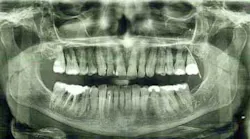

Figure 2a: Panoramic x-ray

Because of my severe bone-loss condition (figures 2 and 2a), I was advised by many offices that my treatment should consist of: extraction, bone grafts, sinus lifts, implants, and crowns. This was very expensive and, I felt, very invasive. I was reluctant, preferring to try to keep my teeth.